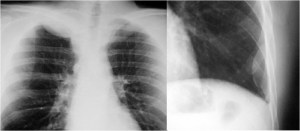

SIGNO DEL TUMOR FANTASMA O TUMOR EVANESCENTE

Signo que describe al derrame pleural atrapado en la cisura menor, especialmente en pacientes con insuficiencia cardiaca. El derrame loculado en la proyección posteroanterior se ve como una lesión nodular o masa que simula un tumor sólido (imagen superior). Sin embargo, la evolución rápida hacia la desaparición de esta lesión sugiere que se trata de derrame.

Vemos en las imágenes un tumor fantasma que desaparece en el control realizado cinco días más tarde.

En la primera imagen, la presencia de derrame pleural asociado y el engrosamiento del resto de la cisura menor, visible como una línea superpuesta al tumor fantasma, sugieren el diagnóstico.